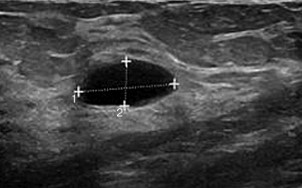

Gambar USG payudara menunjukkan perbedaan antara benjolan jinak dan kanker

Benjolan payudara jinak - dengan margin oval dan terdefinisi dengan baik (permukaan halus seperti anggur)